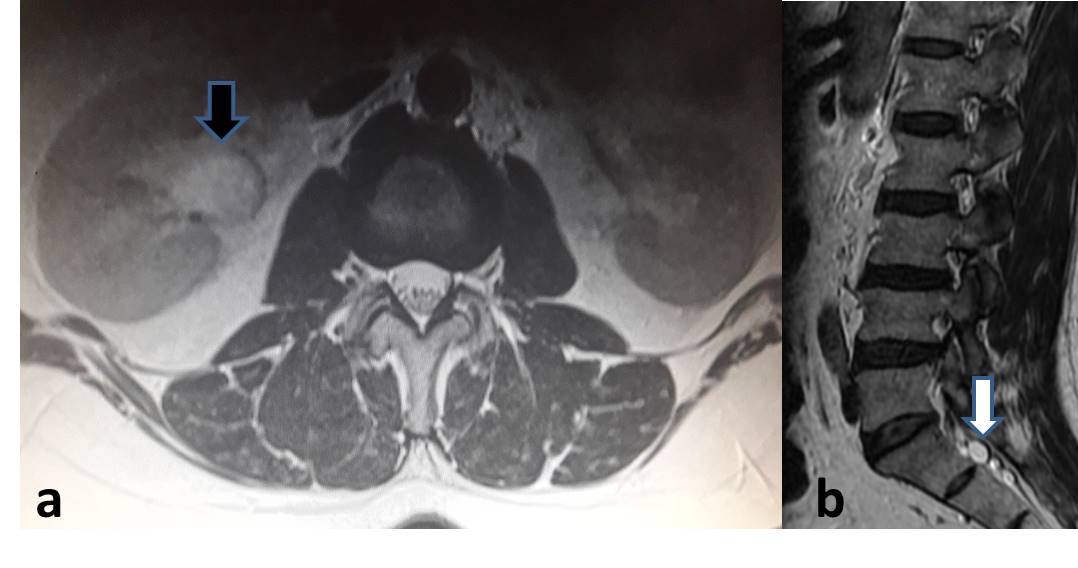

BULGULAR: Toplam 613 hasta (erkek-kadın oranı, 354: 259; yaş aralığı, 16-79 yıl) değerlendirildi. Hastaların % 5.7’ sinde (n=35) vertebra hemanjiomu, % 3.5’inde (n=22) tarlov kisti, % 2.2’ sinde (n=14) böbrek kisti, % 1.4’ünde (n=9) schmorl nodülü, % 0.3’ünde (n=2) karaciğer kisti saptandı.